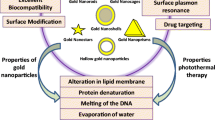

Metal nanoparticles (NPs) such as gold nanostructures [9–12] and carbon nanostructures [13, 14] absorb light and act as photothermal agents and, therefore, improve the efficiency of NIR penetration depth. Also, visible light excitation of metal NPs induces singlet O2 formation and PDT [15]. Among all metallic nanostructures, gold nanostructures are exclusive with remarkable optical properties due to size confinement and surface plasmon resonance (SPR) effects. The frequency of the SPR relies on the size, shape, and dielectric properties of the particles, and gold nanostructures possess adjustable optical properties [16].

In the field of theranostic nanomedicine, multifunctional nanomaterials that combine several abilities are simultaneously employed for diagnosis, follow-up, and treatment of tumors [17, 18]. Gold NP-based multifunctional nanocomposites [19] and carbon nanotube-based nanocomposites [20], like gold/single wall carbon nanotubes [21], are among theranostic agents which employ optical properties of gold nanostructures. Spinel ferrite NPs, with general formula MFe2O4, M = Ni2+, Mn2+, Zn2+, or Co2+, have potential applications for magnetic resonance imaging, cell labeling, drug delivery, and hyperthermia [22]. By combination of magnetic properties of magnetic materials and plasmonic properties of other NPs, theranostic approaches with further therapeutic and diagnostic modalities would be provided [23]. For this purpose, a variety of nanocomposites have been designed. One example is the nanocomposites of iron oxides NPs and cancer-targeting materials [24]. In another study [25], Fe3O4/Au nanocomposite was synthesized to make a multifunctional material with both magnetic and optical properties.

To achieve multimodal imaging, MRI and fluorescence imaging, as well as photothermal ablation, gold nanoshell-based complexes [17], or other composites of gold nanostructures with magnetic materials are among the best candidates.